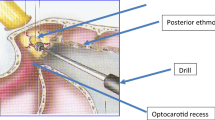

The lateral optocarotid recess represents the pneumatization of the optic strut of the anterior clinoid process. It is located between the osseous prominences of the internal carotid artery (ICA) below and of the optic nerve above.

Optic nerve decompression was then performed from the chiasm to the distal wall of the orbit (the decompression was stopped with the identification of the lamina papyracea and the Zinn annulus). The decompression was obtained with the use of the Hardy dissector and with a high speed microdrill when the bone was too thick.

The following measurements were obtained: intercarotid distance (the median distance between the two CPs) of 12 mm ± 1.5; median length of lateral OCR (which corresponds to the distance between the parasellar carotid artery and the optic nerve) of 5 mm ± 1 (Fig. 1b, c).

In the third phase (optic nerve one), the bony wall surrounding the nerve was removed (Fig. 2a). The average length of optic nerve after decompression was 15 mm ± 2 (Fig. 2b). This measurement was greater than the length of optic canal classically reported in previous anatomical studies.

The explanation of this difference was the extension of the decompression, which was conducted from the orbit to the chiasm, so that the part of nerve exposed was not only the intracanalicular one but also the intracranial and orbit ones. The unfolding of “lamina papyracea” and the Zinn’s annulus confirmed the correct exposure of the orbit (Fig. 2c, d).